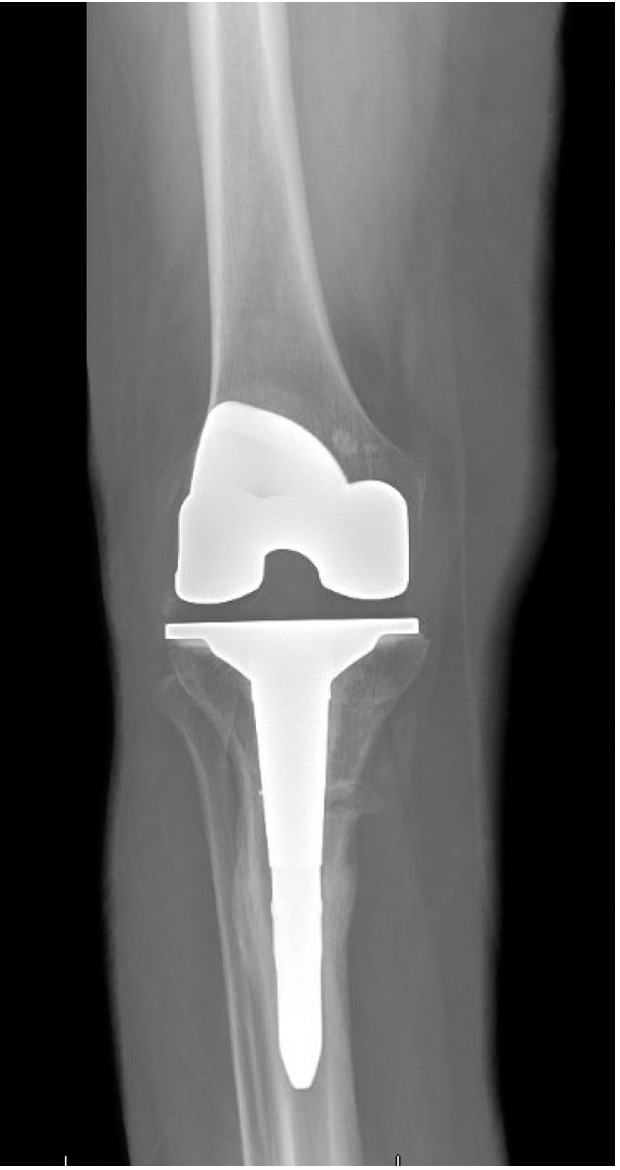

Trial components were inserted and demonstrated balanced flexion and extension gaps and central patellar tracking without the need for lateral release. The tibia was subsequently punched after confirming appropriate rotation for adequate patellar tracking. Final implantation proceeded with pressurized cement for the posterior-stabilized femoral component and the tibial baseplate under tourniquet insufflation. The diaphyseal press-fit stem was again confirmed to span the osteotomy by more than two cortical diameters under fluoroscopic guidance (Figure 4). Autogenous cancellous graft harvested from the femoral chamfer cuts was tightly packed into the osteotomy gap and along the medial cortex. The patella was resurfaced with a medialized polyethylene button.

Quantitative range-of-motion and outcome-score data are summarized in Table 1. At the two-week clinic visit the incision was fully healed and sutures were removed. The patient continued full weight bearing in the brace. By six weeks the osteotomy displayed bridging callus across the osteotomy site (Figure 6), the brace was discontinued, and she achieved an unrestricted gait pattern without assistive devices. Four months after surgery, the patient had resumed activities such as tennis and reported no pain or swelling. Radiographs at that time demonstrated complete cortical union without any interval changes in alignment (Figure 7). At the nine-month assessment she reported hiking up to five miles and skiing on groomed slopes without limitation. Imaging showed continued consolidation of the osteotomy and stable components (Figure 8).